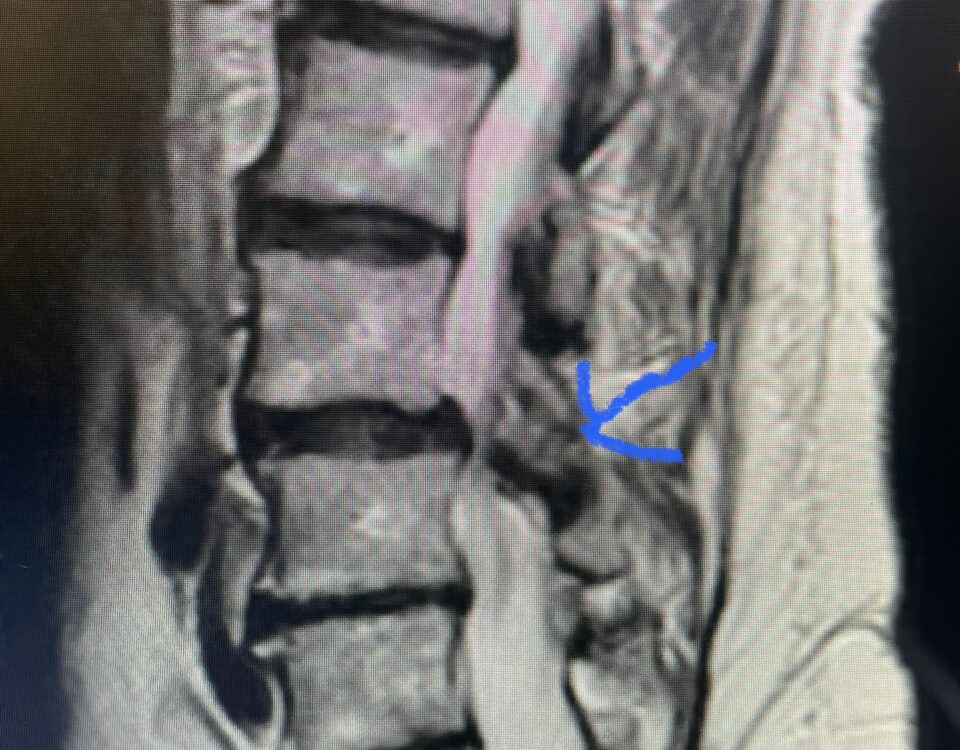

The actual structural cause of lumbar thecal sac compression can vary in degenerative spondylolisthesis and stenosis. The culprits are commonly thickened ligamentum flavum or severe facet […]

After 25 years in practice, I still find it challenging, but quite rewarding: removing degenerative material off the dural membrane in the lumbar spine. Some people […]